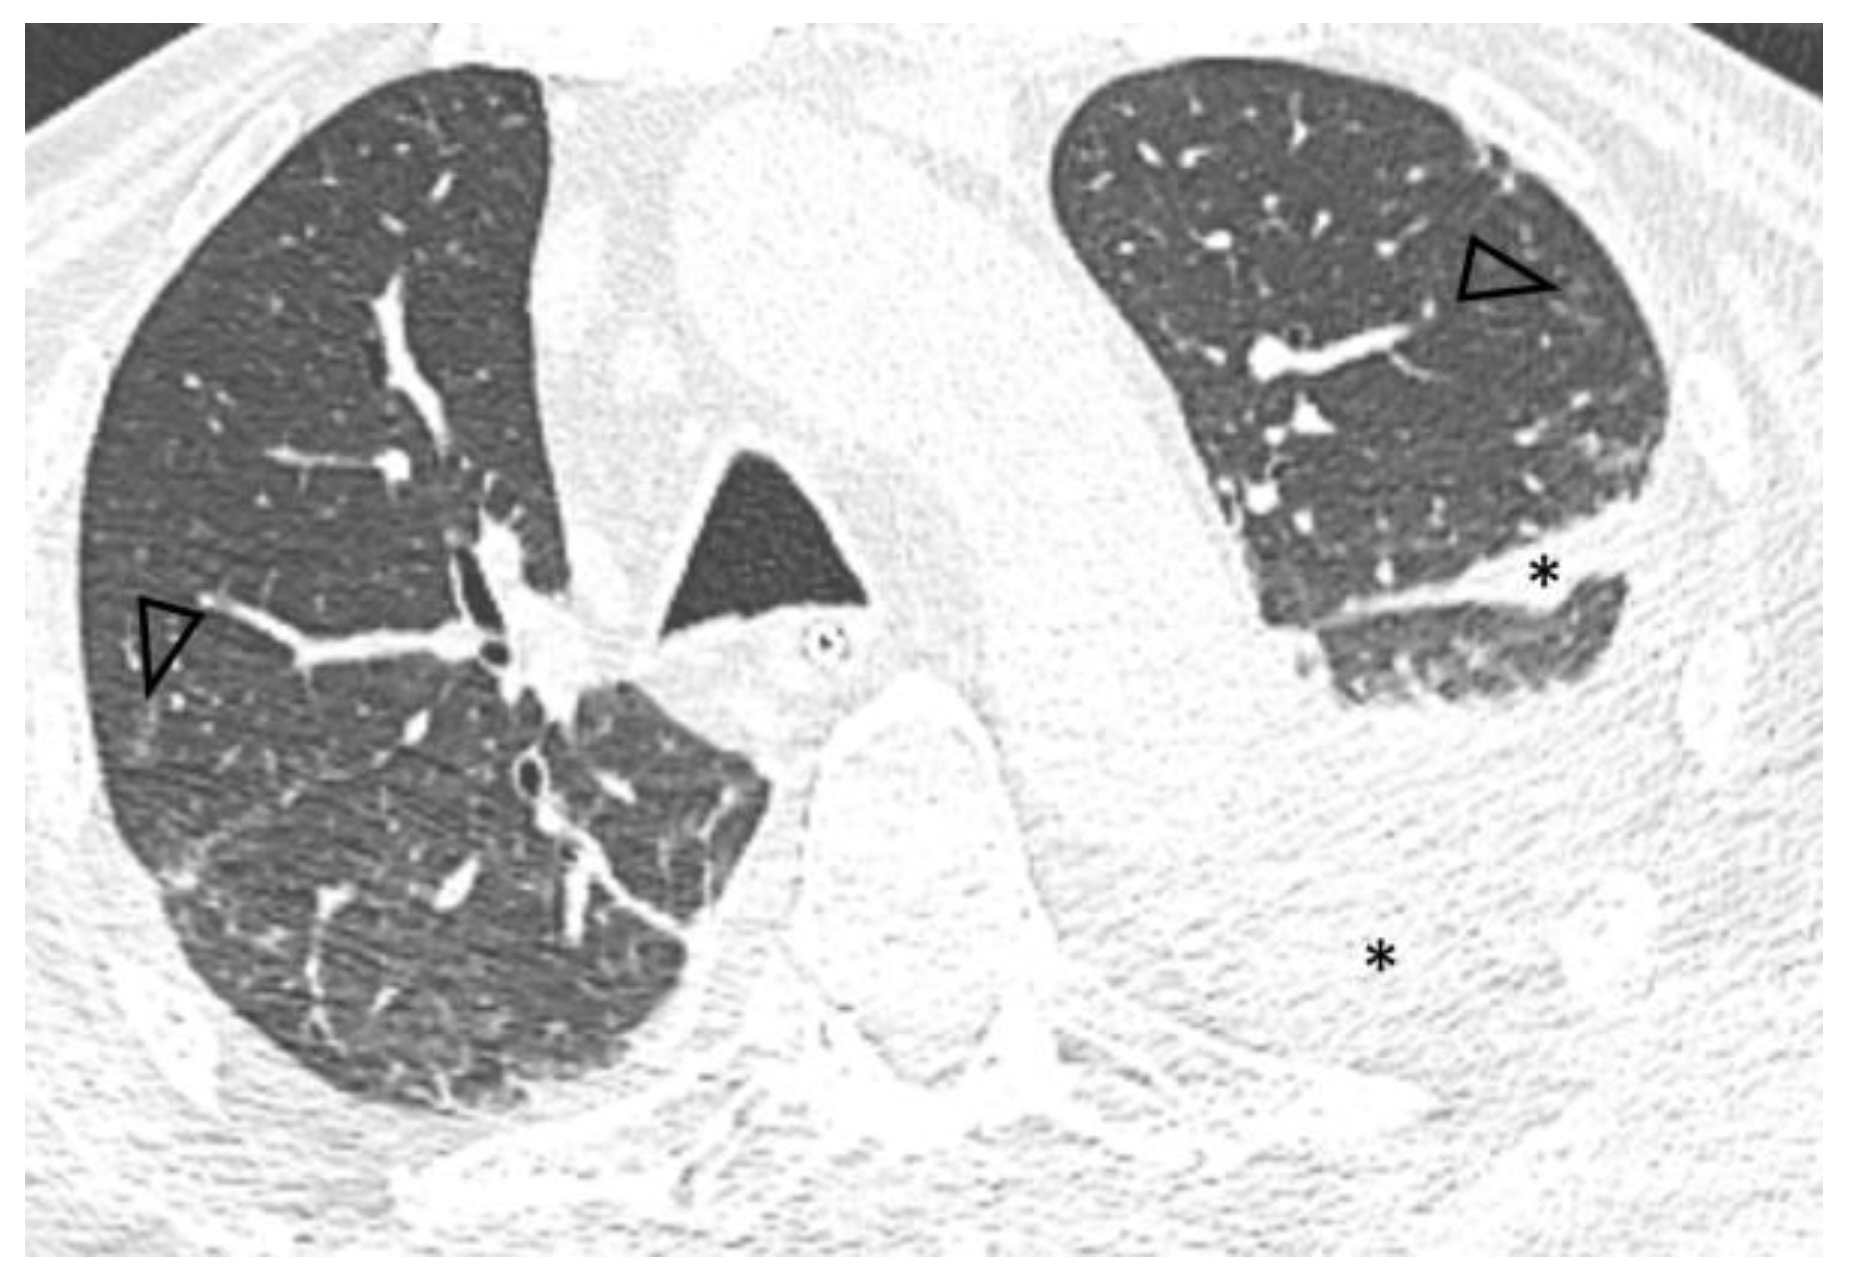

A follow-up chest CT performed five months after diagnosis showed significant improvement of pulmonary disease with subtotal resolution of pre-existing ground-glass opacities and increased pleural effusions (Figure 2).

Figure 2.

Axial 0.6 mm slice, level similar to Figure 1, demonstrates subtotal resolution of opacities with residual centrilobular ground glass nodules (arrowheads) and increased left pleural effusion, extending into the major fissure (*).